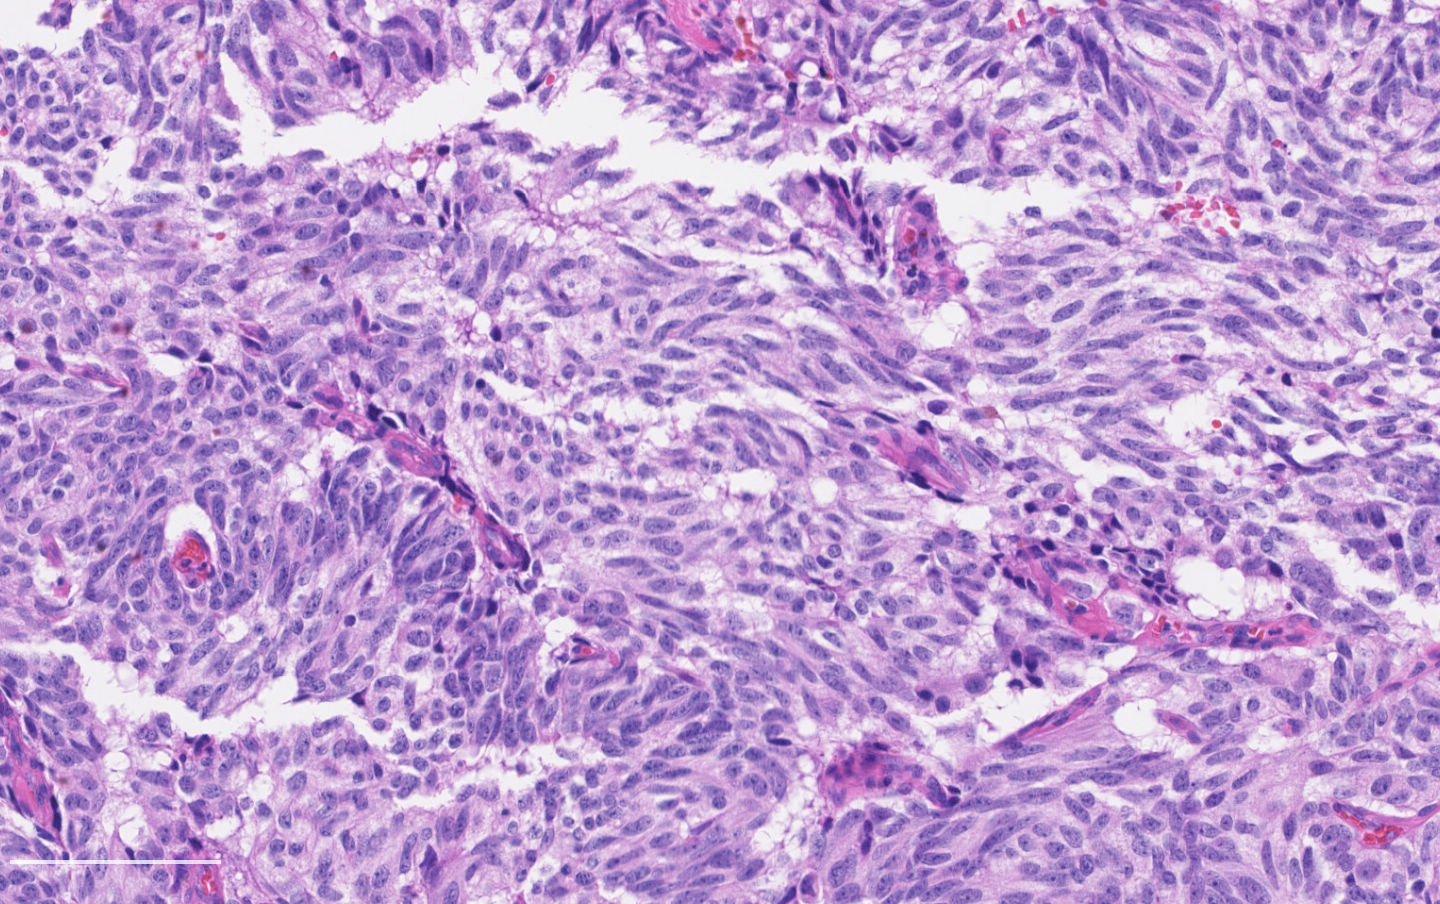

- Neuroendocrine histologic patterns similar to typical carcinoids: organoid, trabecular, rosette formation, papillary, pseudoglandular, follicular

- Tumor cells are as typical carcinoid: uniform with a polygonal shape, round to oval nuclei with salt and pepper chromatin and inconspicuous nucleoli, along with moderate to abundant eosinophilic cytoplasm

- Greater pleomorphism than for typical carcinoid is common (Arch Pathol Lab Med 2010;134:1628)

- Spindle cells and clear cell features can be seen

- Stroma is fine and highly vascularized; hyalinization, cartilage or bone formation are possible

Contributed by Philippe Joubert, M.D., Ph.D.